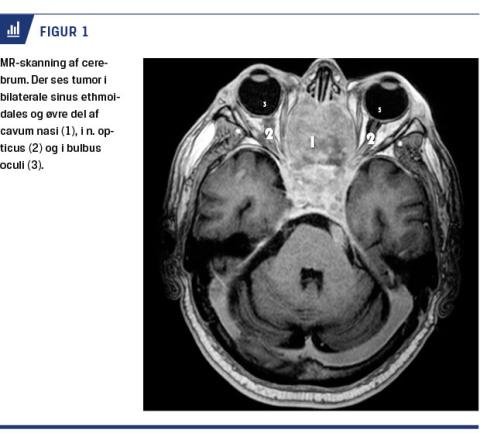

Patienten var uden kendt øjensygdom, og han var, fraset atrieflimren og let hjerteinsufficiens, rask og velbevaret. Han var blevet set af en øjenlæge i akutmodtagelsen på et lokalt hospital efter halvanden måned med fortsat progredierende synstab. Man havde mistanke om tør aldersrelateret maculadegeneration, men grundet tiltagende synstab på begge øjne henvendte patienten sig flere gange i akutmodtagelsen i de efterfølgende uger. Der blev foretaget CT og taget blodprøver på mistanke om arteritis temporalis eller occipitalt infarkt. På CT sås forandringer, der blev tolket som fibrøs dysplasi, og udtalt sløring af sinus ethmoidalis, sinus sphenoidalis og sinus frontalis bilateralt foruden en uregelmæssig forkalket proces, som bulede ind i begge orbitae. Der blev foretaget MR-skanning på mistanke om kompression af n. opticus, og på skanningen sås der en tumor bilateralt i etmoidalcellerne og sfenoidet og med tumorvækst ind i begge canales optici, hvilket medførte kompression af begge nn. optici (Figur 1). Patienten blev set på øre-næse-hals (ØNH)-afdeling på mistanke om sinonasal cancer.